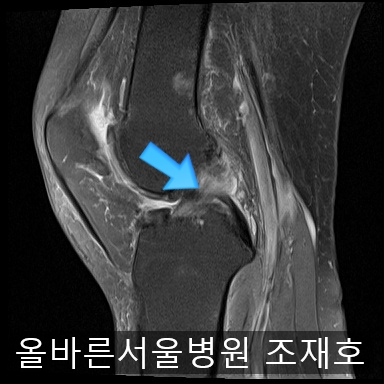

为了掌握具体情况拍了MRI。

image_2475163911519368491057.jpg

髌骨关节虽有炎症,但仍保留相当一部分软骨。

内侧关节软骨几乎不见,软骨板也受损严重。软骨损伤部位充满关节液。